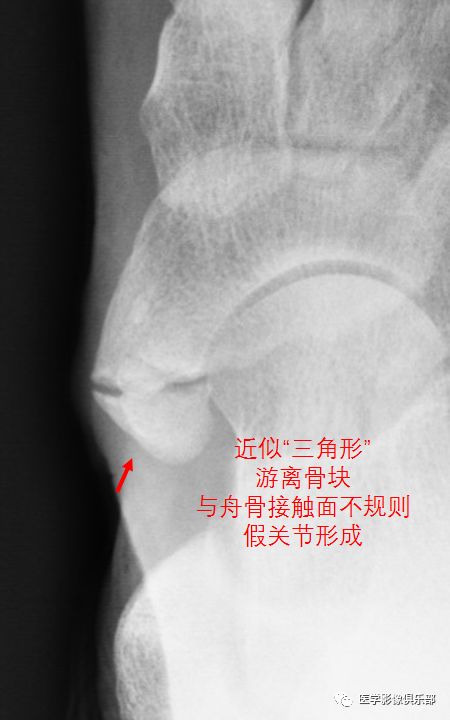

2型副舟骨和舟骨结节间以纤维软骨相连,受到外伤后关节损伤,出现炎症。